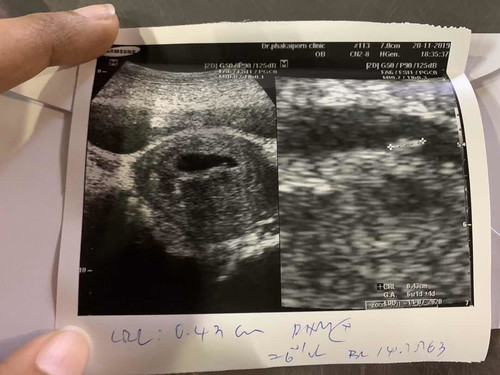

หาตัวเด็กไม่เจอ // เจอถุง2ถุง เป็นถุงเลือดที่อาจจะแท้ง

>>หมอบอกว่า 6 w ตอนแรกซาวหาเด็กไม่เจอ แต่ซูมดูเจอตัวเล็กๆ แบบนี้ปกติมั้ยคะ เล็กเกินไปรึป่าว แต่เจอหัวใจเต้นแล้ว >> และเจอ 2 ถุง แต่อีกถุงเป็นคล้ายๆถุงเลือด หมอถามว่าปวดท้องบ้างมั้ย เราปวดท้องค่อนข้างบ่อย มีสิทธิ์จะแท้ง กังวลมากเลย